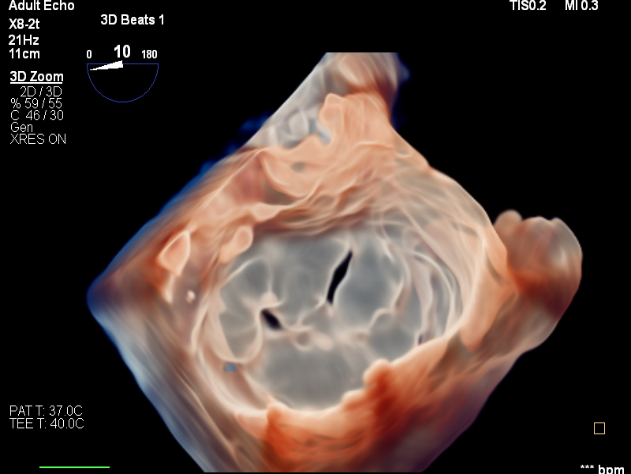

回顾性分析61例重度MR患者在TMVR术前和术后6个月行经食管三维超声心动图检查(所有手术均采用第一代MitraClip系统进行)。其中:功能性MR(FMR)(n=45)和器质性MR(OMR)(n=16)。使用三维超声心动图软件MVQ对MV几何结构进行量化分析。随访术后6个月时的缩流颈面积(VCA)确定两个结果组:VCA<0.6cm²(MR<0.6)为效果良好组和VCA≥0.6cm²(MR≥0.6)为复发组。

通过MVQ分析得出的MV几何体的3D参数。